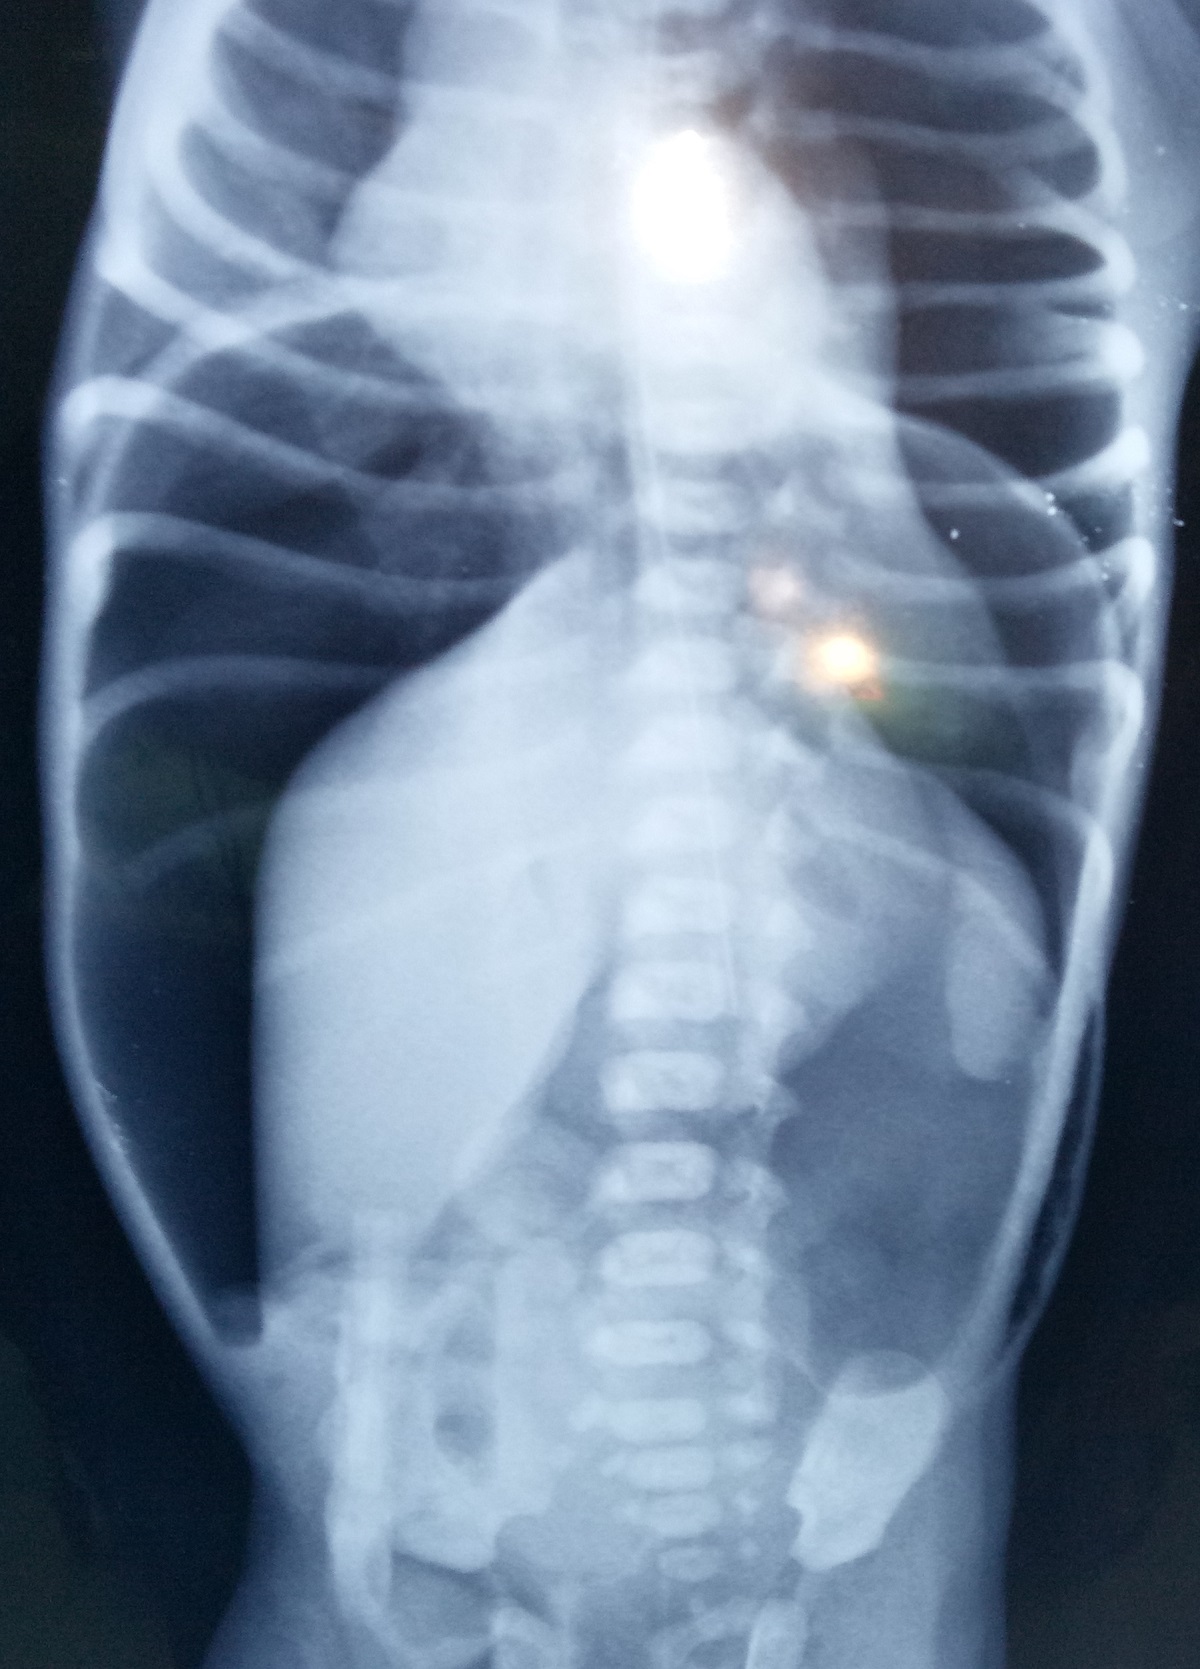

A 2-day-old male term neonate born of uncomplicated pregnancy and normal vaginal delivery at a private hospital was referred to us with progressively increasing abdominal distension in the last 16 hours of life. He was breastfed once and had passed a small amount of meconium once at 10 hours of life. At presentation, he was dehydrated, tachypneic (RR 43/min), tachycardia (HR 146/min), and had delayed capillary refill time (4 sec). Babygram showed a large amount of air under the diaphragm (Fig. 1). Laboratory investigations were as: Hb 12.7 g%, total leukocyte counts of 18000/cmm, C reactive proteins 80 mg/L, platelets 2.3 lacs/cmm, urea 34 mg/dl, creatinine 0.9 mg/dl, Na 131 meq/l and K 2.3 meq/l. Blood culture sent at admission was later found to be sterile. After initial resuscitation, he underwent exploratory laparotomy that revealed a large gastric perforation near the postero-lateral wall of greater curvature (Fig. 2). The rest of the bowel was healthy. The perforation site was primarily repaired.

Figure 1

X-ray abdomen showing huge pneumoperitoneum.